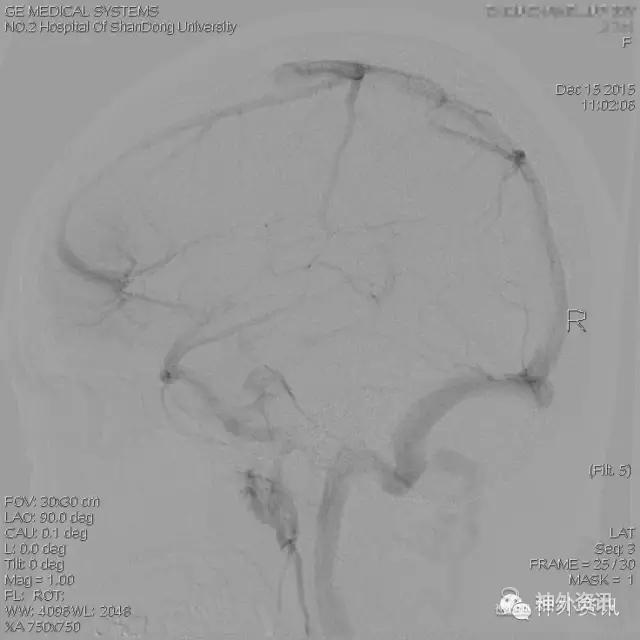

住院后行DSA检查。

右侧颈内动脉正位造影,右额叶动脉期、毛细血管期未见明显异常。

静脉期显示右额顶叶无明显静脉引流。

静脉窦期显示粗大的引流静脉汇入上矢状窦。

右颈内侧位,动脉期、毛细血管期、静脉期未见明显异常。

静脉窦期显示右额叶粗大引流静脉,由数条脑小静脉汇聚而成,呈“水母头样”,引流向上矢状窦后部。

右颈外造影排除硬脑膜动静脉瘘等异常。双侧椎动脉造影未见明显异常(图片略)。

2. 其在DSA上的典型表现是仅仅在血管造影的静脉期、静脉窦期可以看到,而在动脉期或毛细血管期,由于其没有早期静脉引流而不显影,这点与AVM或动静脉瘘不同。静脉畸形可以伴有脑实质的异常,包括脑组织局部萎缩或相邻白质病变。13-18%的静脉畸形伴有海绵状血管瘤。